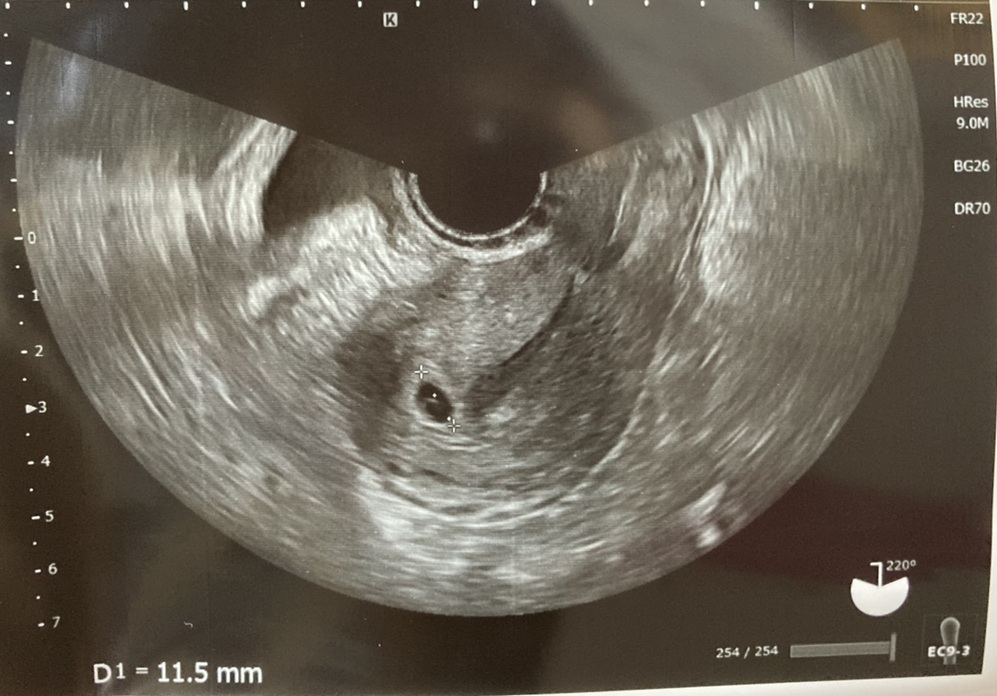

ほぼ一週間後である3/13(BT21日目)に受診したところ、胎嚢がみえました!

なんとか子宮内に着床してくれたことがわかり、泣けました。

その後、3/19(BT27日目)に卵黄嚢と胎芽を確認できました。